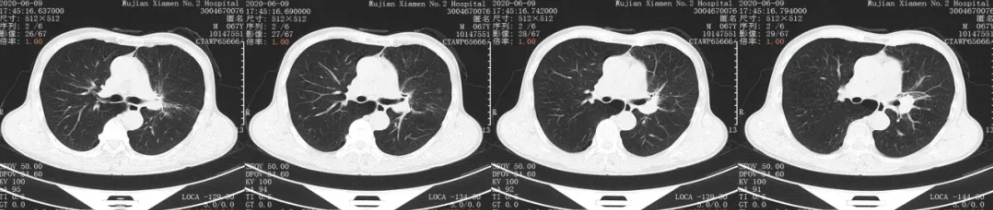

行31个周期免疫维持治疗

一线维持治疗用药方案:卡瑞利珠单抗 200mg

胸部CT平扫+增强:2021年10月复查

胸部CT平扫+增强:用药31个周期后复查

疗效评价:SD

后续治疗:考虑专家推荐免疫治疗2年,目前患者病情稳定,建议停用免疫维持,进行观察